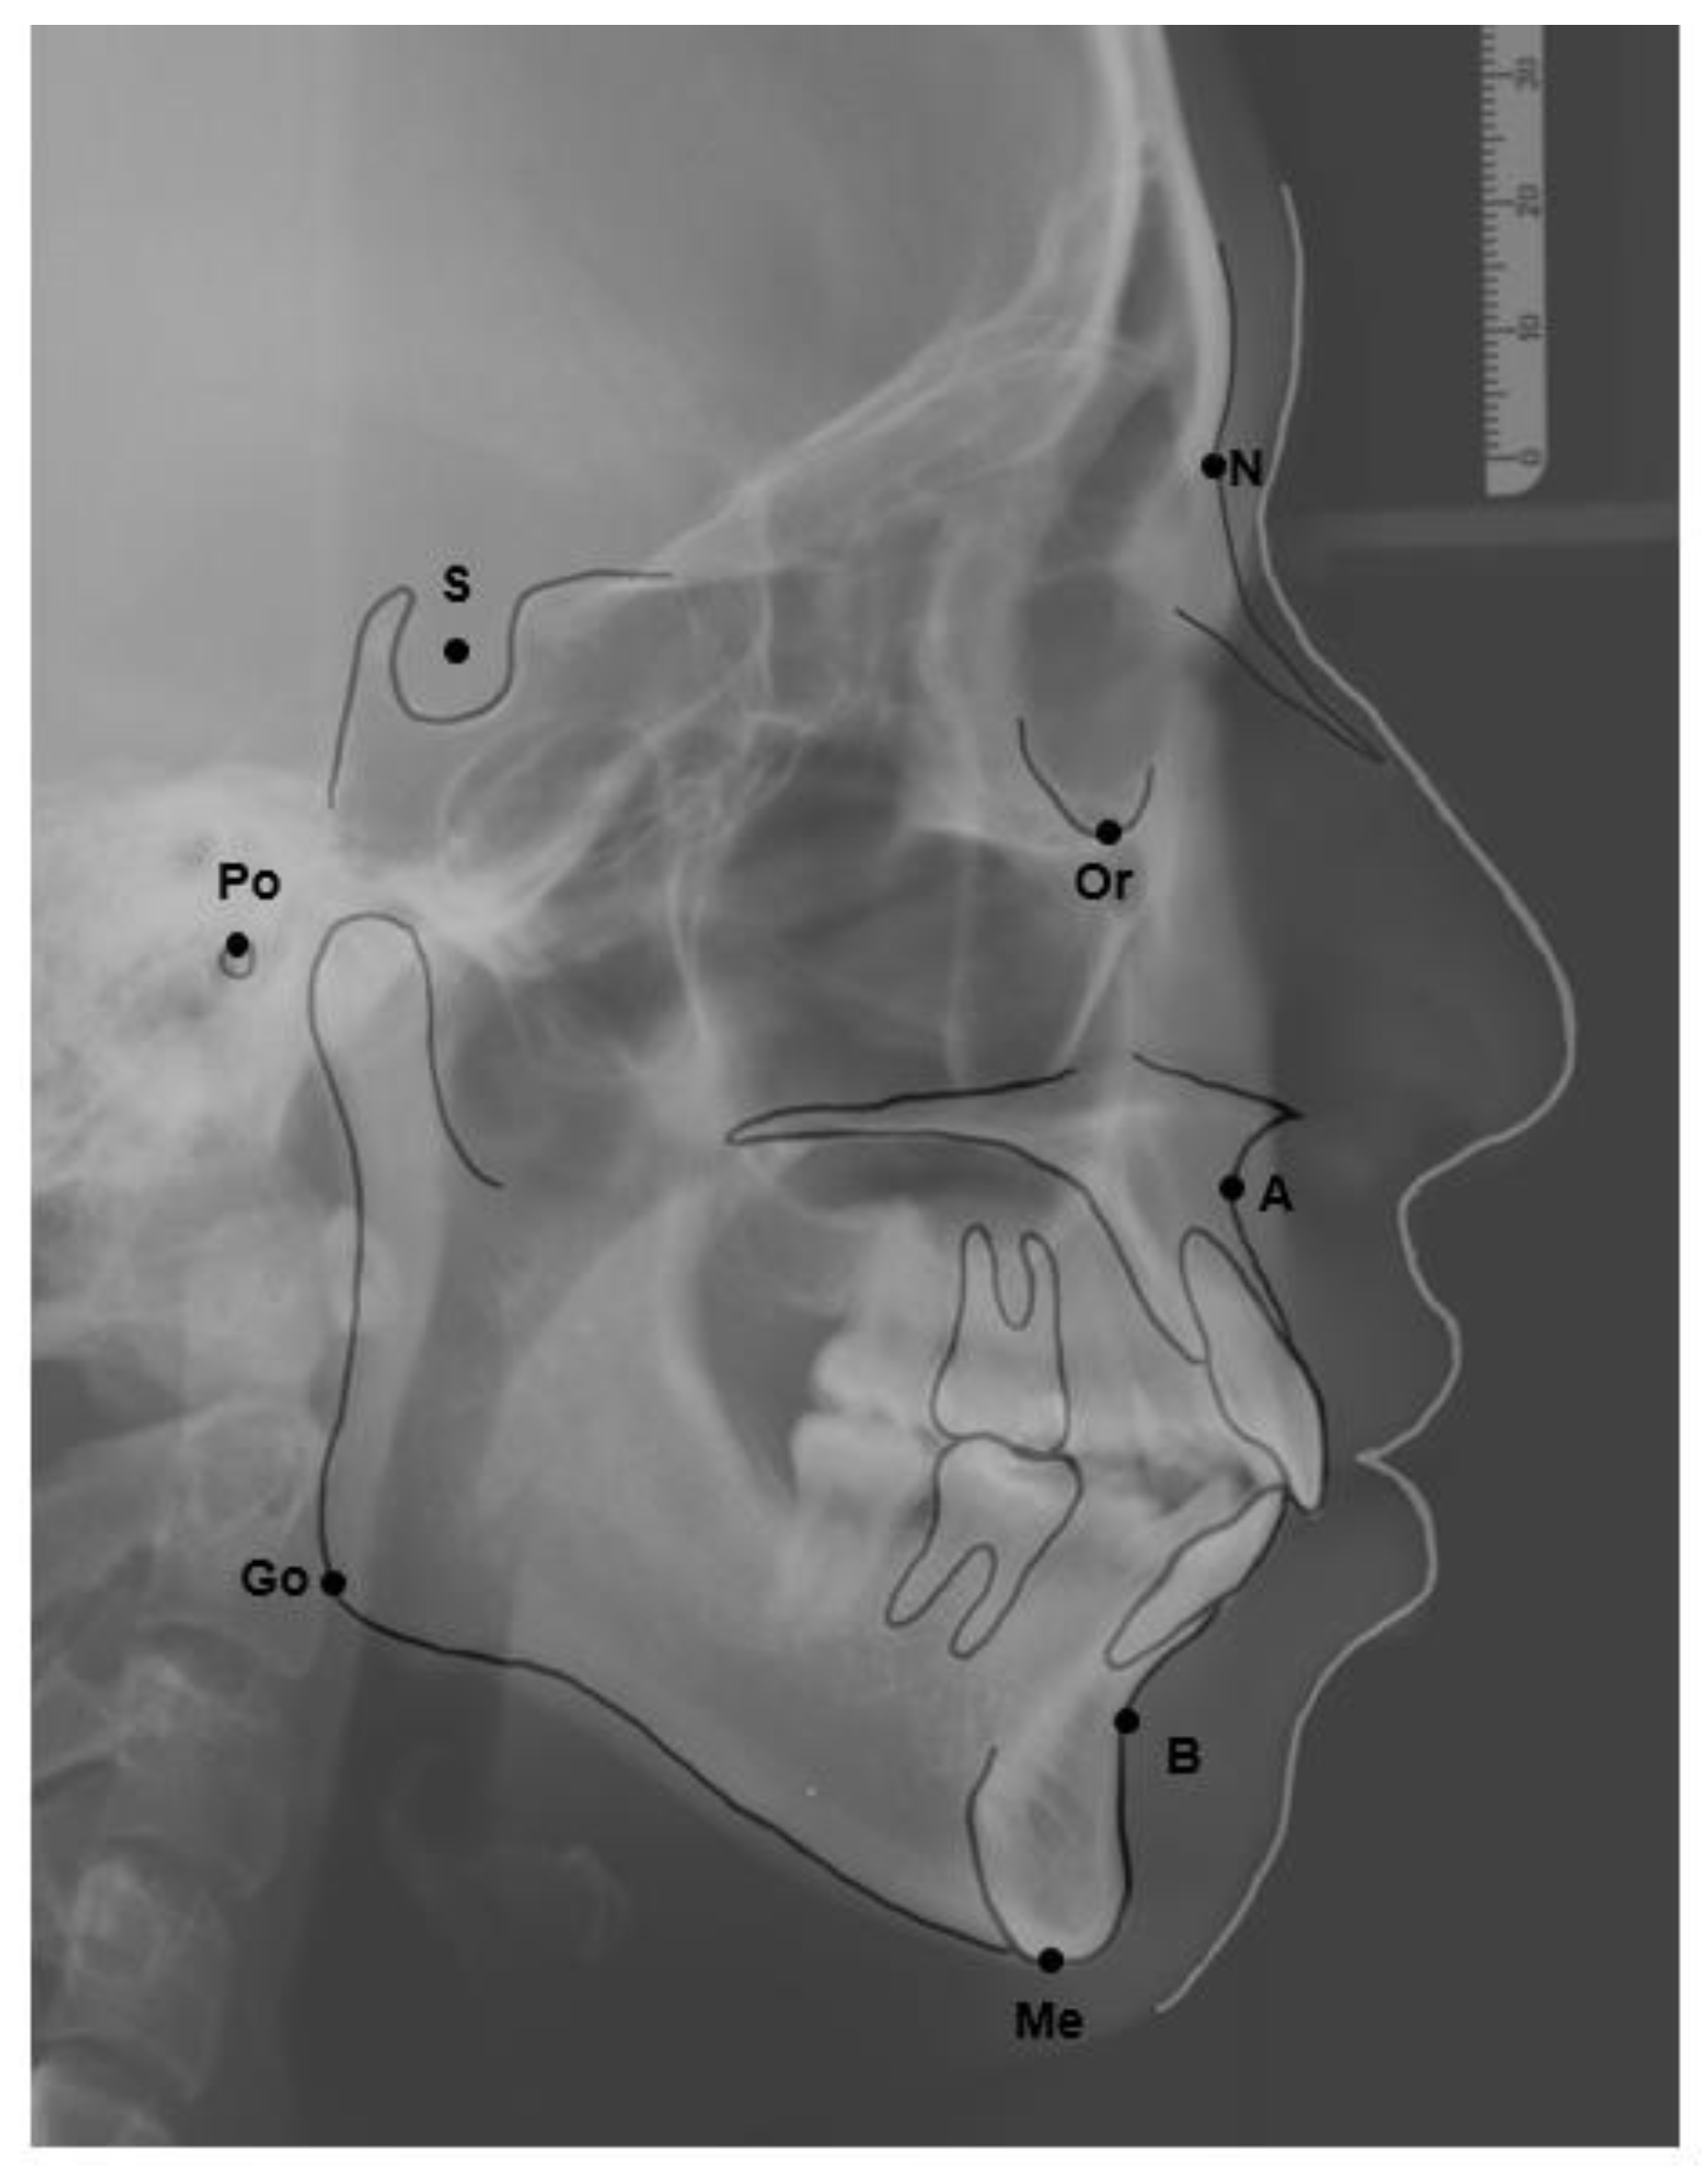

The skeletal relationship between the maxilla and mandible of orthodontic patients was categorized as Class I, Class II, or Class III [35,36,37,38] (Figure 1 and Figure 2). Steiner’s analysis [39] and Tweed analysis [40] were used for the measurements according to the analysis of St. Louis University in the United States, where the first author was trained for her orthodontic graduate program. The dental relationship between the maxilla and mandible of orthodontic patients was defined as molar Class I, Class II, or Class III (Figure 3). The DMFS index was expressed as the total number of teeth that were decayed (D), missing (M), or filled (F) in an individual with permanent dentition. There were five surfaces (facial, lingual, mesial, distal, and occlusal) for the posterior teeth and four surfaces (facial, lingual, mesial, and distal) for the anterior teeth when the DMFS index was calculated.

Figure 2. Sagittal skeletal classification based on ANB angle. ANB: The angle is constructed by connecting the A point, nasion, and B point. According to the Steiner analysis, the measurement represents the skeletal relationship between the maxilla and mandible. (a) Class I relationship: ANB is between 2 and 4. (b) Class II relationship: ANB is greater than 4. (c) Class III relationship: ANB is below 2 or negative.